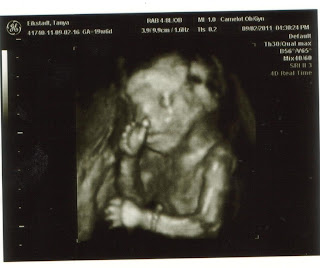

The nice thing was that I was able to have an ultrasound while waiting my hour. We were checking for little man's growth. A few weeks ago we thought he was a BIG baby. It appears that now he is right on track. He is growing fast and ahead of schedule a bit, but they say that means nothing as far as delivering early. Yesterday he weighed about 1lb 15oz. I'm guessing today we are closer to the 2lb mark. He's right on track...so nothing to worry about. And we can finally see some baby fat being added to that tiny skeleton. He doesn't look as bony now and it seems that he likes to suck his thumb/fingers.